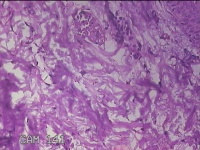

右侧腰臀部包块

性别

女

年龄

44岁

临床诊断

臀部良性肿瘤

一般病史

发现右侧腰臀部包块1个月余。

标本名称

大体所见

灰白粉红色包块0.8x0.3x0.2cm一个,表面光滑。

良性病变。